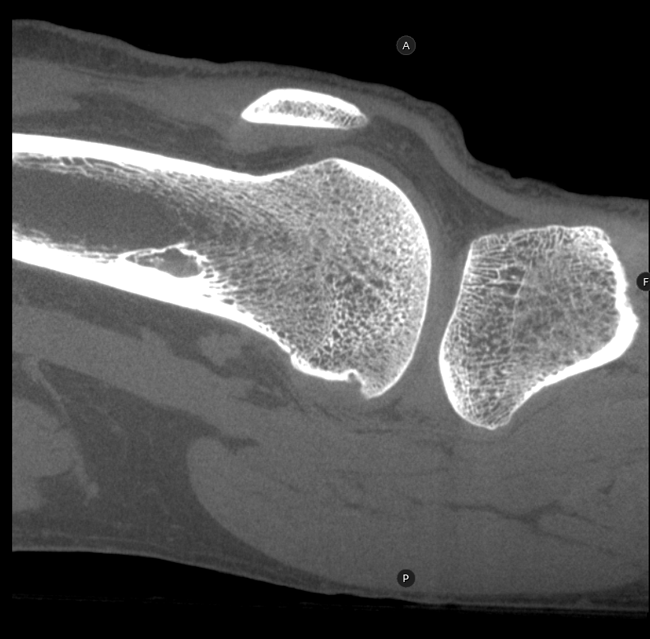

HRCT

High Resolution Computed Tomography. Outstanding image quality with a voxel size up to 100 µm